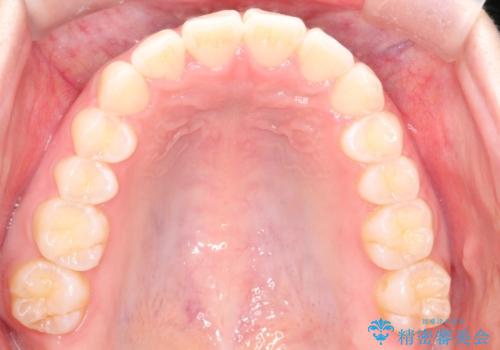

【インビザライン】前歯が出ているのを治したい

- 前歯が出ていることを主訴に来院されました。

前歯の突出感が改善され、満足していただきました。